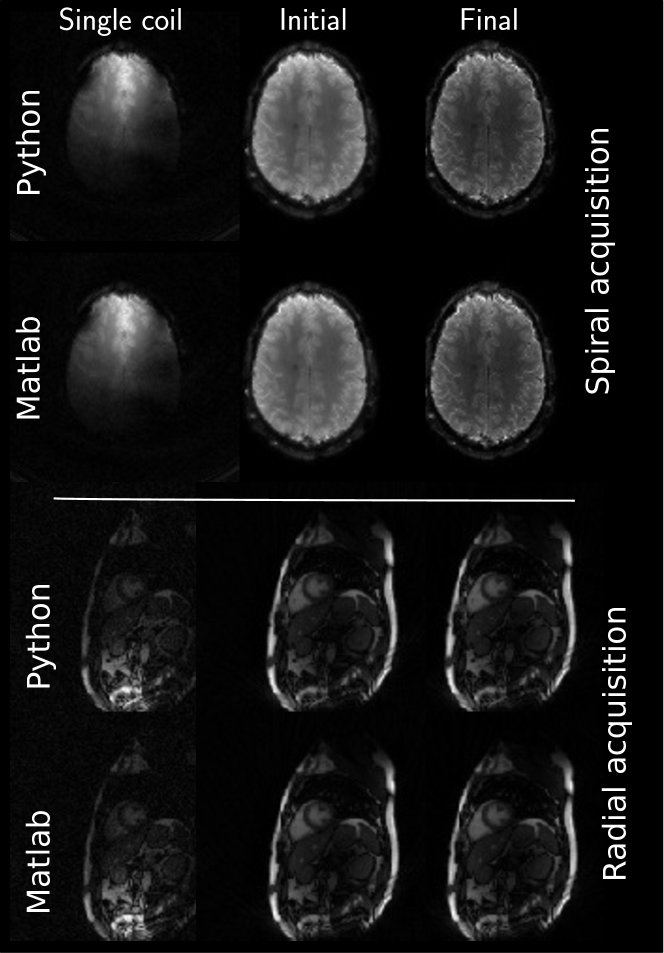

For the heart data, more differences are observed. Firstly, FOV differences occur more frequently (Eindhoven - cropped to 320x320, ETH - cropped to 360x360, NYU - cropped to 300x300, Stanford - asymmetric crop to 240x336). Secondly, matrix size in the same FOV and thus resolution is changed by some submissions (Berkeley - 300x300, USC - 256x256, Utah - 320x320). The heart reconstruction results for 11 spokes from Berkeley seem to be more noisy than the others. The reconstructions using the reference implementations, are given in Figure 4 and Figure 5 for Python and Matlab, respectively. Neither intensity nor contrast variations are visible between the two reference implementations.

Finally, Figure 9 shows the two additionally supplied data sets. Both reference methods are able to produce clean images and visually, no differences can be observed.

Figure 4: Consolidated reconstruction results using the Python implementation.

Refer to caption

Figure 9: Example reconstruction results of the two additional supplied data sets. Top rows show the spirally acquired brain data set and bottom rows show radially acquired cardiac data. Both reconstructions included noise pre-whitening prior to reconstruction from a dedicated noise scan preceding image acquisition. Windowing is performed between the minimum and maximum intensity value in each image.